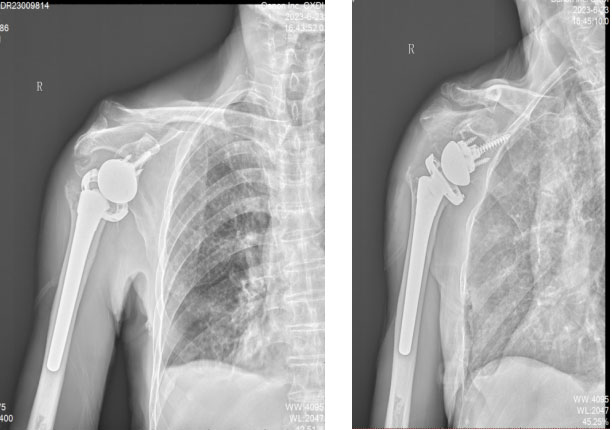

5.术后X片。